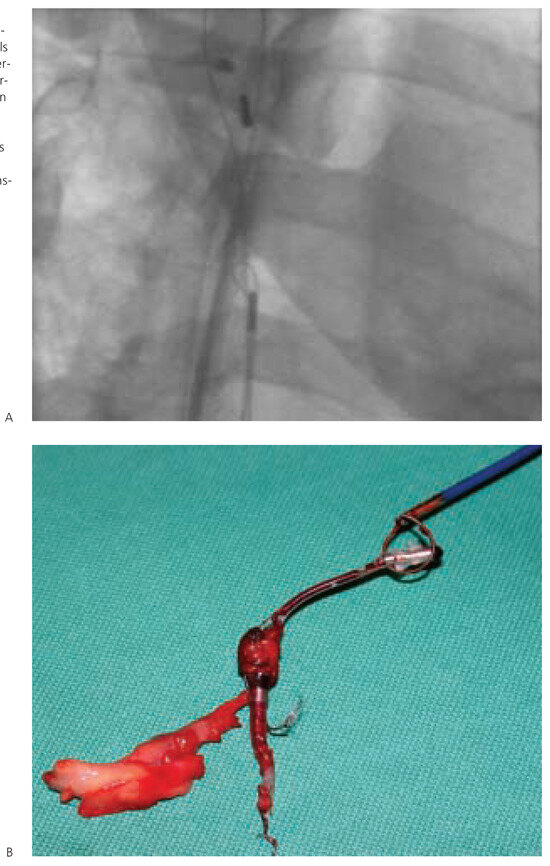

This article gives an overview on the practical management of device infections of chronically implanted pacemakers and implantable cardioverter- defibrillators. The main feature of such infections is the fact that the implanted materials have direct contact with the bloodstream, and therefore, may rapidly [...] Read more.

This article gives an overview on the practical management of device infections of chronically implanted pacemakers and implantable cardioverter- defibrillators. The main feature of such infections is the fact that the implanted materials have direct contact with the bloodstream, and therefore, may rapidly progress to systemic infection with serious septic complications. Apart from aggressive antibiotic treatment, in general, the infected material has to be explanted. Therefore, it is helpful to differentiate between the isolated pocket infection with the option of local surgical revision under preservation of the implanted leads and the systemic infection with the necessity of complete removal of all implanted materials using either the lead-extraction technique or open heart surgery. Full article